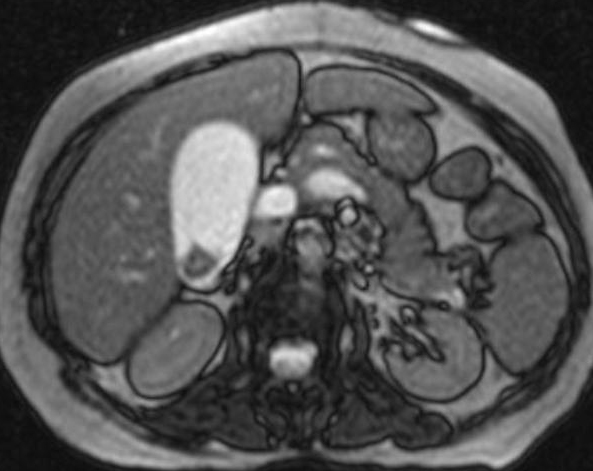

Image IRM et

cholangio -IRM ( MRCP ) : Image de calcul

de la vesicule biliaire est lacule a hyposignal dans

la vesicule remplie de liquide hyperintense

Calcule vesicule biliaire

hypointense a infundibulum de la vesicule

hyperintense . Image IRM ponderee en T2 coupe axiale

|